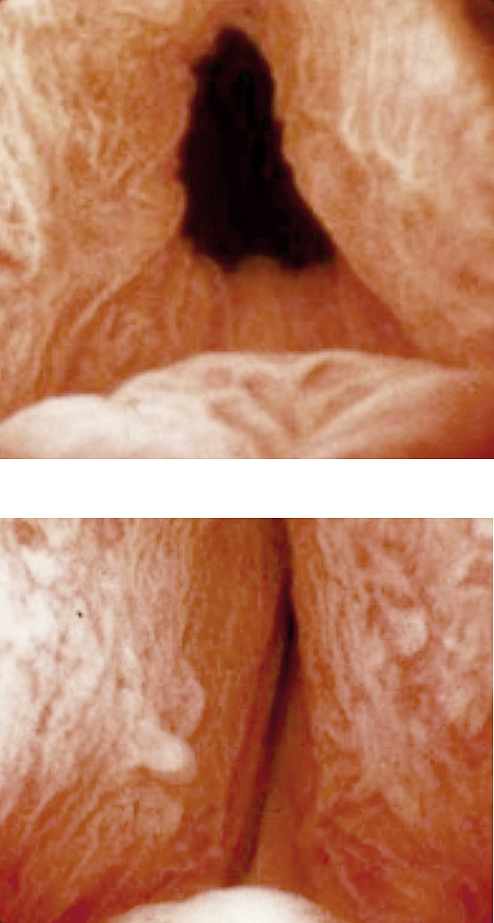

cyctoscopy - blocked urethra

Using a cystoscope, the physician can verify how much urine flow is impaired.

• Cystoscopy to look at the urethra or bladder with a scope